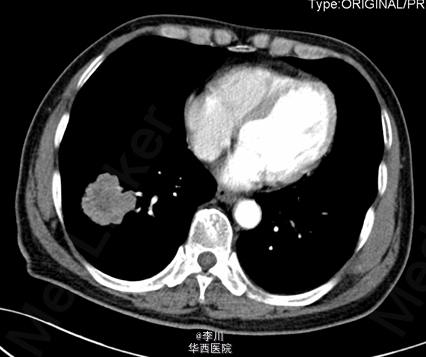

患者男,73岁,因“咳痰伴痰中带血2+月”入院。患者于2+月前无明显诱因出现咳痰伴痰中带血,无咳嗽、胸闷、胸痛等症状,未予以处理。10+天前于外院就诊,行胸部CT、心脏超声、纤支镜等检查示:右肺占位。予以口服及输液治疗13天(具体不详),症状无明显好转。

于全麻下行“VATS右肺下叶切除术+淋巴结清扫术”,术中见:肿块块位于右肺下叶,约4.2*3.9cm大小,脏层胸膜皱缩、无侵犯壁层胸膜;术中冰冻结果:(右下肺肿块)腺癌。

肺癌的分叶征是周围型小肺癌最常见的基本征象。其病理基础一是与肿瘤边缘各部位肿瘤细胞分化程度不一,生长速度不同有关;二是肺的结缔组织间隔,进入肿瘤的血管、支气管分支、从肿瘤内向外生长的血管和结缔组织等引起肿瘤生长受限并产生凹陷,从而形成分叶的形态。分叶征对于鉴别肺部包块良恶性具有重要价值。